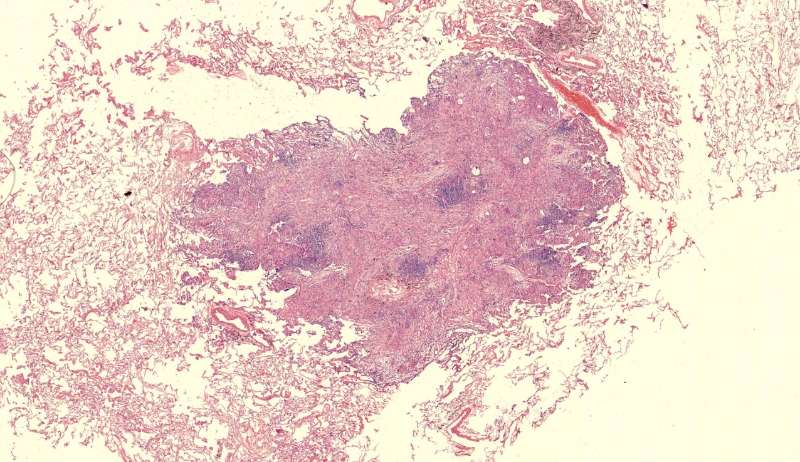

第二例隐球菌

整体是个类圆形,边界模糊(有晕征的感觉),肉芽肿一般都这样 里面也能见到许多小白球,大小从3微米到20微米不等 红细胞直径5-6微米 普通小淋巴细胞直径5微米 这里淋巴细胞挺多 有许多淋巴细胞,成堆

多核巨噬细胞吞了许多隐球菌 经常是反包围的感觉